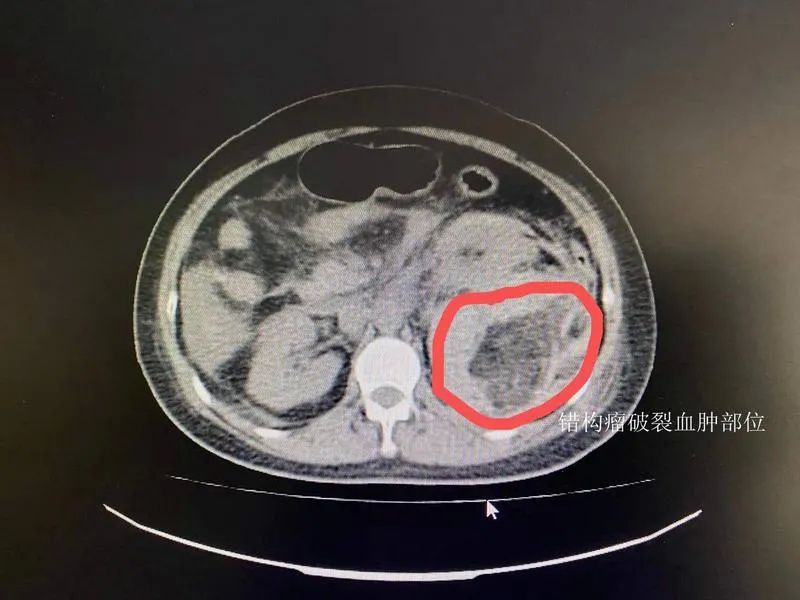

经CT检查发现李女士左肾出血

医生考虑为左肾错构瘤破裂出血

▲李女士CT检查影像

医生随即为李女士安排急诊检查,发现李女士血红蛋白、血小板含量均低于正常值,完善全腹CT发现左肾后方存在包块,盆腔有大量积液(血),双侧胸腔也存在积液。